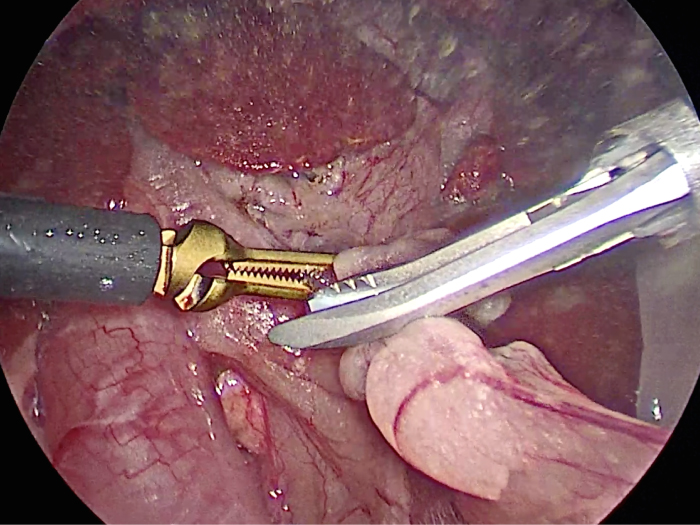

丁寧に丁寧に出血をコントロールしながら少しずつ手術をすすめていきます。

このように癒着しているときはギリギリで剥がすとひどく出血をおこすことがあるので無理にはがそうとしないで、脂肪の血管に注意しながら脂肪ごと剥がしていきます。

胆嚢は分厚くなり周りには脂肪が張り付いていました。

胆嚢の頸部に糸を通し動脈を確保しています。

胆嚢を少しずつ丁寧に肝臓から剥がしています。